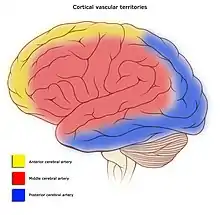

Areas of the brain are supplied by different arteries. The major systems are divided into an anterior circulation (the anterior cerebral artery and middle cerebral artery) and a posterior circulation | |

Blood supply to the brain is normally divided into anterior and posterior segments, relating to the different arteries that supply the brain. The two main pairs of arteries are the Internal carotid arteries (supply the anterior brain) and vertebral arteries (supplying the brainstem and posterior brain).[2]. The anterior and posterior cerebral circulations are interconnected via bilateral posterior communicating arteries. They are part of the circle of Willis, which provides backup circulation to the brain. In case one of the supply arteries is occluded, the circle of Willis provides interconnections between the anterior and the posterior cerebral circulation along the floor of the cerebral vault, providing blood to tissues that would otherwise become ischemic.[3]

Anterior cerebral circulation

The anterior cerebral circulation is the blood supply to the anterior portion of the brain including eyes. It is supplied by the following arteries:

- Internal carotid arteries: These large arteries are the medial branches of the common carotid arteries which enter the skull, as opposed to the external carotid branches which supply the facial tissues; the internal carotid artery branches into the anterior cerebral artery and continues to form the middle cerebral artery. [4]

- Anterior cerebral artery (ACA)

- Anterior communicating artery: Connects both anterior cerebral arteries, within and along the floor of the cerebral vault.

- Middle cerebral artery (MCA)

Posterior cerebral circulation

The posterior cerebral circulation is the blood supply to the posterior portion of the brain, including the occipital lobes, cerebellum and brainstem. It is supplied by the following arteries:

- Vertebral arteries: These smaller arteries branch from the subclavian arteries which primarily supply the shoulders, lateral chest, and arms. Within the cranium the two vertebral arteries fuse into the basilar artery.

- Basilar artery: Supplies the midbrain, cerebellum, and usually branches into the posterior cerebral artery

- Posterior cerebral artery (PCA)

- Posterior communicating artery